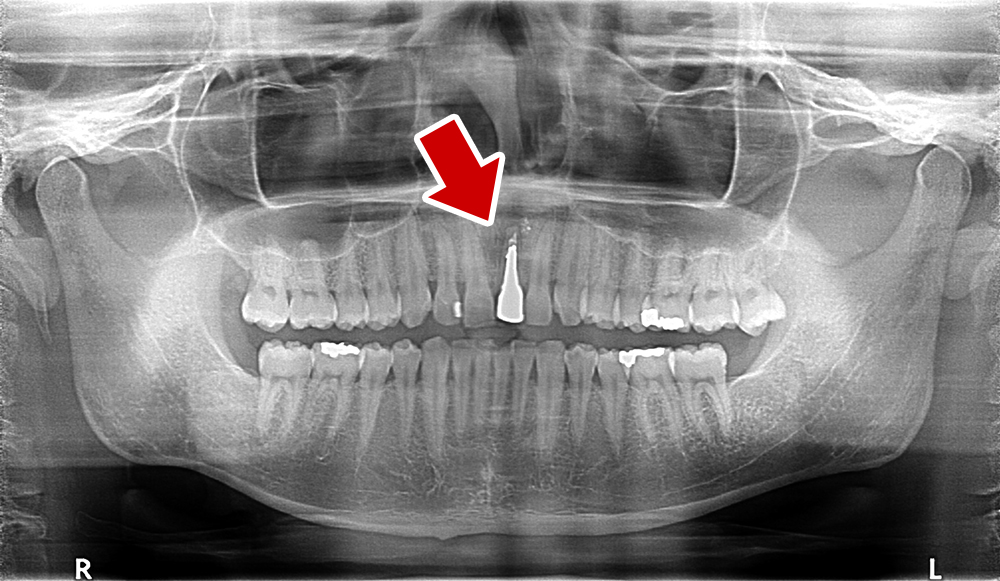

29歳 男性 歯科医療関係者紹介。また、お姉さんが歯科医療関係者。

- 主訴

- 左上1番目の歯が長期にわたり痛く、噛めない。

- 処置内容

-

1本インプラント埋入+再生療法。抜歯即時埋入、即時荷重法⇒抜歯を行い、

同時にインプラント埋入(即時埋入)、そして同時にインプラントへ仮歯を装着(即時荷重)

歯が無い期間なく、社会生活に支障が出ない

- 治療費用

- 約39万円(税込)

- 治療期間

9か月

手術当日に人工歯(仮歯)まで装着。 (通常待機期間は1年必要です。 (抜歯後6か月+インプラント(根)待機期間6か月+仮歯2か月))

- リスク

- 上部構造物、仮歯の破折、術後の腫れ(3日)、人工歯根脱落リスクがあります

- その他

- 学術雑誌、海外公演(アメリカ、ヨーロッパ)に多く紹介されたケース